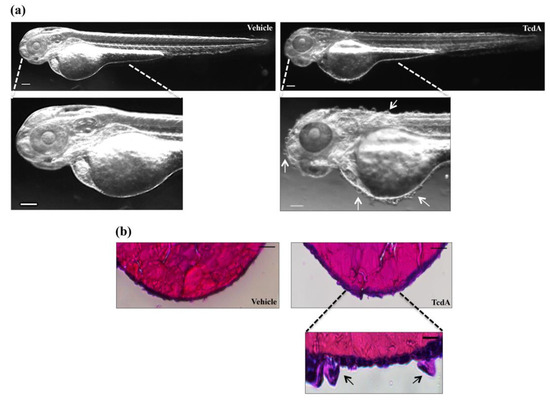

3.5. TcdA Induces Skin Alteration in Zebrafish Embryos

A peculiar feature associated only with TcdA treatment was a significant alteration of the skin that appeared bullous throughout the body (Figure 7a, right panel, white arrows). Histological analysis of TcdA-treated embryos showed thickened skin and hypertrophy of some cells of the outermost layer of the epidermis shown by arrows in Figure 7b (lower-right panel). In contrast, no changes in the skin structure of TcdB-treated embryos were observed.

Figure 7.

TcdA administration induced skin alteration in zebrafish embryos. (a) Representative images of 2.5 µg/mL TcdA- or vehicle-treated embryos. Images were acquired with a Leica S8AP0 stereo microscope. Scale bar = 100 µm. (b) Hematoxylin and eosin staining is performed on 2.5 µg/mL TcdA- or vehicle-treated embryos to evaluate skin structure. Scale bar = 100 µm (upper panel). A magnification of the hypertrophic cell of the epidemical layer is taken from TcdA-treated embryo (lower panel; scale bar = 10 µm). Images were acquired with a Leica S8AP0 stereo microscope.

A peculiar morphological effect associated only with TcdA treatment is the presence of bubbles on the embryo’s skin surface (Figure 7a, lower-right panel, white arrows). Moreover, the hematoxylin and eosin staining shows that the outermost layer of the epidermis in TcdA-treated embryos appeared thickened compared to vehicle-treated ones (Figure 7b, lower-right panel, black arrows). Nevertheless, no skin alterations directly caused by C. difficile have ever been reported in patients with CDI. Thus, the effects observed in zebrafish embryos after TcdA administration could be a specific response of the model to the intoxication.